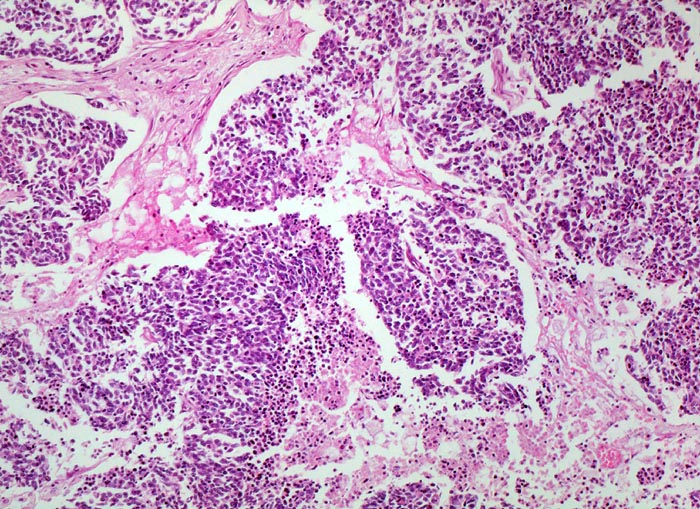

Die monomorphen rundlichen, fusiformen oder polygonalen Tumorzellen haben sehr wenig Zytoplasma, die Kerne sind hyperchromatisch und Nukleolen sind kaum zu erkennen. Die Tumorzellen bilden lockere Verbände, bandförmige Anordnungen oder Pseudorosetten um Gefässe. Oftmals zeigen die Tumoren in der Biopsie charakteristische Quetschartefakte. Ein histologisches Grading wird im Gegensatz zu den nicht kleinzelligen Karzinomen nicht vorgenommen. An kleinen Biopsien kann die morphologische Unterscheidung eines kleinzelligen Karzinoms von einem Lymphom bzw. von normalem lymphatischem Gewebe schwierig sein (> 1101). Diese Unterscheidung gelingt aber meist problemlos mit Hilfe einer immunhistochemischen Zusatzuntersuchung (> 1100).

• Drei Bronchialschleimhautbiopsien ausgekleidet von respiratorischem Flimmerepithel.

• Blauer, sehr zelldichter solider Tumor in der Submukosa des mittleren Biopsiefragmentes. Die beiden anderen Schleimhautfragmente sind tumorfrei.

• Tumorzellen mit sehr schmalem Zytoplasmasaum ("nacktkernig").

• Sehr zahlreiche Apoptosen und kleinherdige Tumornekrosen.